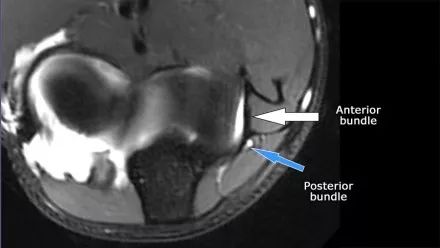

在研究韧带时,尤其是UCL,始终使用轴向图像。如果你看内侧上髁,你会发现后束是一个薄的结构(蓝色箭头)。注意在肘管内的尺神经。

后束形成肘管隧道的地板。支持带覆盖肘管。请注意,前束更厚(白色箭头)。您可以看到前韧带和后韧带之间的区别,即使它们形成一条韧带。走向远端,我们会看到它们合并在一起以附着于崇高的结节。